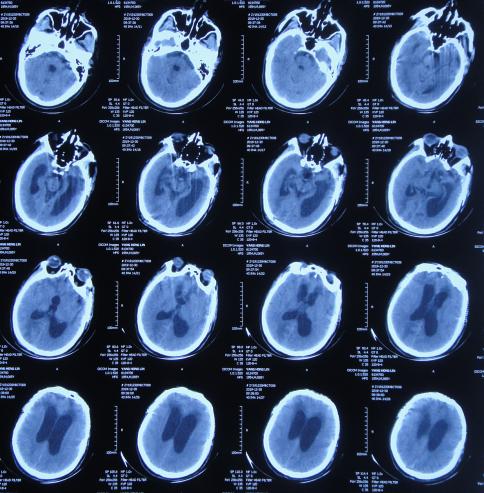

继续治疗1周时间内,曾3次复查头颅CT( 图-5、图-6、图-7 )均示脑膨出逐渐加重的趋势,仍有积血;期间给予腰大池引流。

图-5: 2019年10月26日头颅CT

图-6: 2019年10月29日头颅CT

图-7: 2019年10月31日头颅CT

开颅术后14天即2019年11月3日,虽仍有些积血,但脑膨出有好转( 图-8 ),意识也变清。

图-8: 2019年11月3日头颅CT

开颅术后18天即2019年11月7日,脑膨出进一步好转( 图-9 )。

图-9: 2019年11月7日头颅CT

开颅术后26天即2019年11月15日,查头颅CT示积血基本消失,脑膨出变正常( 图-10 )。

图-10: 2019年11月15日头颅CT